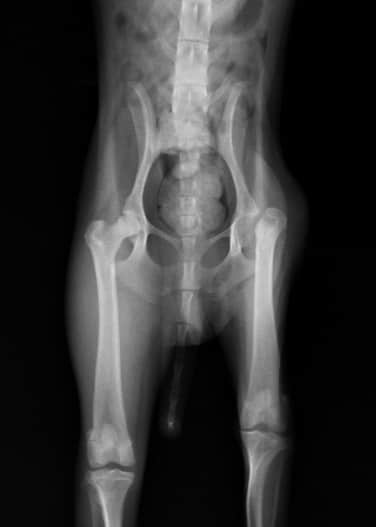

2、X线检查

从图中可清晰看见病变股骨头已经被完全切除,切除后的股股头断端光滑、整齐,生长良好。